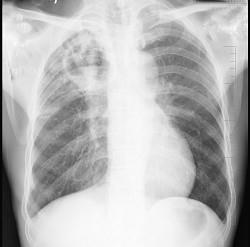

问题 男性,63岁,咳嗽、发热1个月,消瘦、乏力明显,既往有肺结核史,X 线检查如图,最合理的诊断是 ( )

选项 A.右肺炎 B.右肺结核Ⅲ型 C.右肺结核Ⅳ型 D.右肺脓肿 E.右间质性肺炎

答案 B